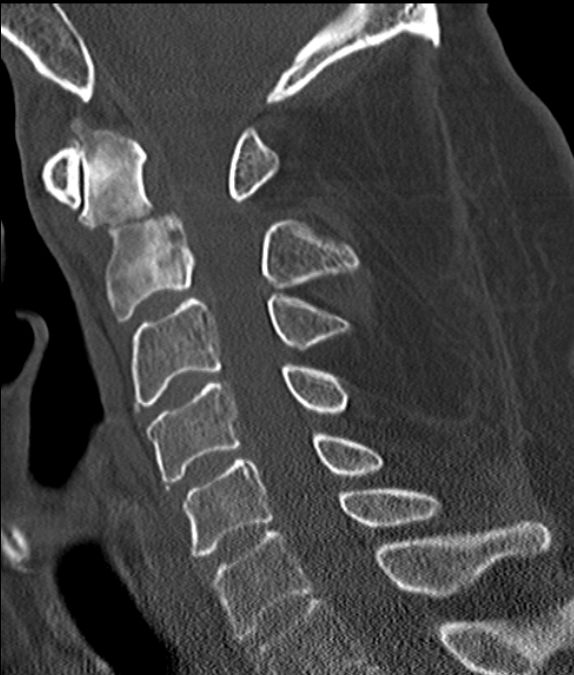

75-jähriger Mann, der wegen unklarer Schmerzen im

Nackenbereich abgeklärt wurde. Als Ursache der Knochenmetastasen wurde ein lokal

fortgeschrittenes Prostatakarzinom (PSA 143, Gleason 7) gefunden.![]() |

Das T2-Bild im MRT der HWS zeigt eine

Signalverstärkung im 7.HWK. Der Densbereich ist stark umgebaut.![]() | |||||||||||||||||||